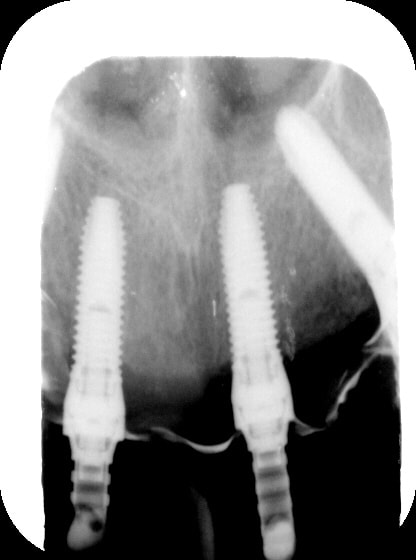

PJ les RX du jour

rx du haut...8 mois après...

Gin8m1 wfymdg - Eugenol

Gin8m2 rdbaga - Eugenol

Gin8m3 zsapdx - Eugenol